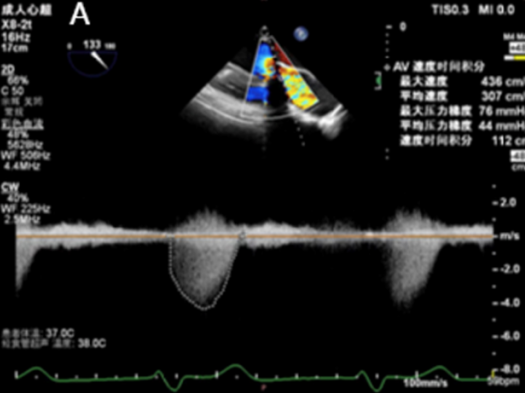

该患者为83岁男性,11年前植入的主动脉瓣(圣犹达医疗21mm)和二尖瓣(圣犹达医疗27mm)生物假体退化,导致充血性心力衰竭,左心室射血分数(LVEF)为40%,合并重度主动脉瓣狭窄/关闭不全及重度二尖瓣关闭不全。症状包括不明原因的胸闷、喘息、端坐呼吸和持续的夜间阵发性呼吸困难。检查发现心律失常、频繁早搏,二尖瓣/主动脉瓣区可闻及4/6级收缩期杂音。经胸/经食道超声心动图(TTE/TEE)确认二尖瓣生物假体重度反流[缩流宽度(VCW)8mm,平均跨瓣压差8mmHg],主动脉瓣生物假体重度狭窄/反流(平均跨瓣压差44mmHg;峰值流速5.7m/s,缩流宽度8mm)(图1)。其他检查发现左心房明显扩大,LVEF40%,中度肺动脉高压(估测收缩压57mmHg)。冠状动脉造影未见明显异常。术前心脏计算机断层扫描测量主动脉瓣环尺寸为周长58.6mm,面积252.9mm²,直径18.1mm,并发现右冠状动脉高度偏低(6.4mm)。二尖瓣瓣环直径24mm,主动脉-二尖瓣角度为61.8°,计算新左心室流出道面积为999.9mm²,提示经导管二尖瓣瓣中瓣(TMViV)术后左心室流出道梗阻风险较低。NT-proBNP显著升高(11363.03pg/mL)。由于患者高龄、既往胸骨切开术和合并症,传统再次主动脉瓣置换(AVR)或二尖瓣置换(MVR)风险过高。多学科团队在获得患者知情同意后,决定采用ScienCrown自膨式瓣膜同期进行经心尖主动脉瓣瓣中瓣(TAViV)及二尖瓣瓣中瓣(TMViV)植入术。

图1. 生物瓣膜假体功能的超声心动图评估。A:主动脉瓣生物假体严重狭窄伴反流(平均压差44mmHg;峰值流速5.7m/s ,VCW 8mm )。B:二尖瓣生物假体严重反流(VCW 8mm ,平均压差8mmHg)。